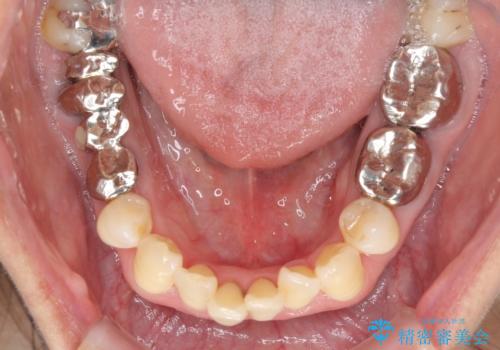

- 上の前歯の変色と、下の前歯のデコボコを気にして来院された患者様です。

補綴治療に先立ち、下顎前歯の部分矯正を行い、前歯の咬み合わせの安定性向上を図りました。

当初は上顎の補綴治療のみを希望されていましたが、奥歯にブリッジなど補綴物が多くあり、前歯も変色しているため、治療費が高額となってしまうことが懸念されました。

相談の上、最も気になっている前歯の部分矯正と補綴治療により口元の改善を図ることとしました。